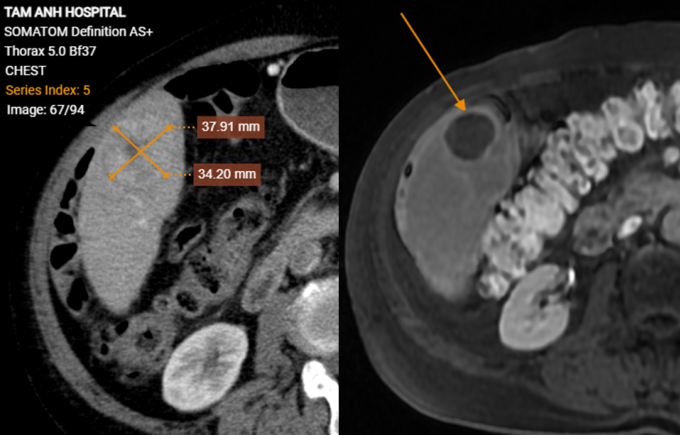

Ông Phong không có triệu chứng bất thường, siêu âm tầm soát ung thư gan do hút thuốc hơn 30 năm, tiền sử xơ gan, viêm gan siêu vi B, kết quả có khối giảm âm trong gan. Xét nghiệm máu ghi nhận mức AFP (chỉ điểm ung thư gan) trên 1440 ng/ml, gấp hơn 200 lần ngưỡng bình thường. Ảnh chụp CT phát hiện hai khối u gan kích thước 15×20 mm và 37×34 mm, bệnh nhân còn bị lóc tách động mạch chủ ngực, xơ vữa, phình, giãn một số động mạch chủ khác và hẹp 56% gốc động mạch thân tạng.

Khối u gan của bệnh nhân Phong trước (bên trái) và sau điều trị đã hoại tử (bên phải). Ảnh: Bệnh viện Đa khoa Tâm Anh

Tái khám sau ba tháng, kết quả chụp MRI ghi nhận hai khối u gan bệnh nhân giảm đáng kể kích thước, không còn ngấm thuốc, các tế bào ung thư đã hoại tử. Ông Phong có sức khỏe tổng thể tốt, tăng cân, chỉ số AFP giảm về ngưỡng bình thường 6,5 ng/ml, đáp ứng hoàn toàn với điều trị, theo bác sĩ Hiền.